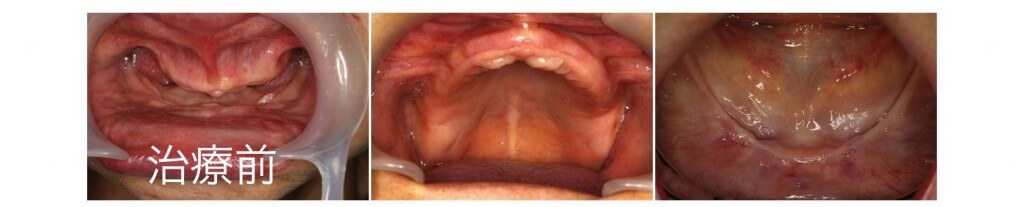

下顎の著しい骨吸収を伴う無歯顎症例です。下顎の顎堤は吸収し義歯の安定が望めない状態です。こうした場合には顎堤の前方部分に複数のインプラントを埋入し連結する事で大臼歯部までの歯列を完成させる事が可能となります。

手術当日に仮義歯を固定する事でその日から安定した咬み合わせを手に入れる事ができました。